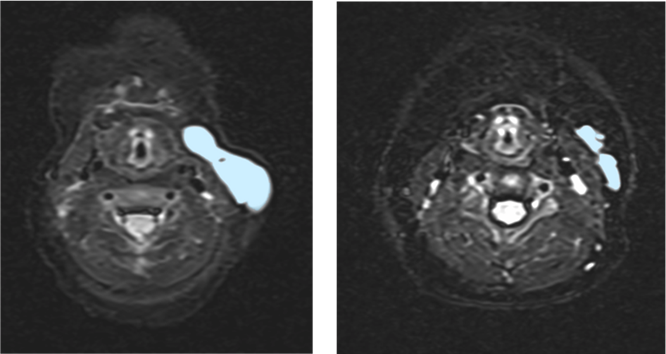

本研究では、体重25kg 以下の小児19 人に越婢加朮湯を6 か月間投与し、その効果を調べました。MRI により画像検査を行ったところ、52.6%の症例で病気の部分が20%以上縮小し、顔や首回りでは83.3%の小児に効果が見られました。副作用は軽度なものが多く、重い副作用を発症したのは1 人だけでした。また、薬の継続率も高く、約9 割が実際にきちんと飲まれており、多くの子どもが継続して治療を受けら

れたことがわかりました。

本研究は、広島大学病院を中心に、金沢大学、慶應義塾大学、大阪大学、日本大学、国立成育医療研究センター、昭和医科大学、聖マリアンナ医科大学、全国8 施設が共同で実施しました。MRI 画像解析は中央判定により行われました。